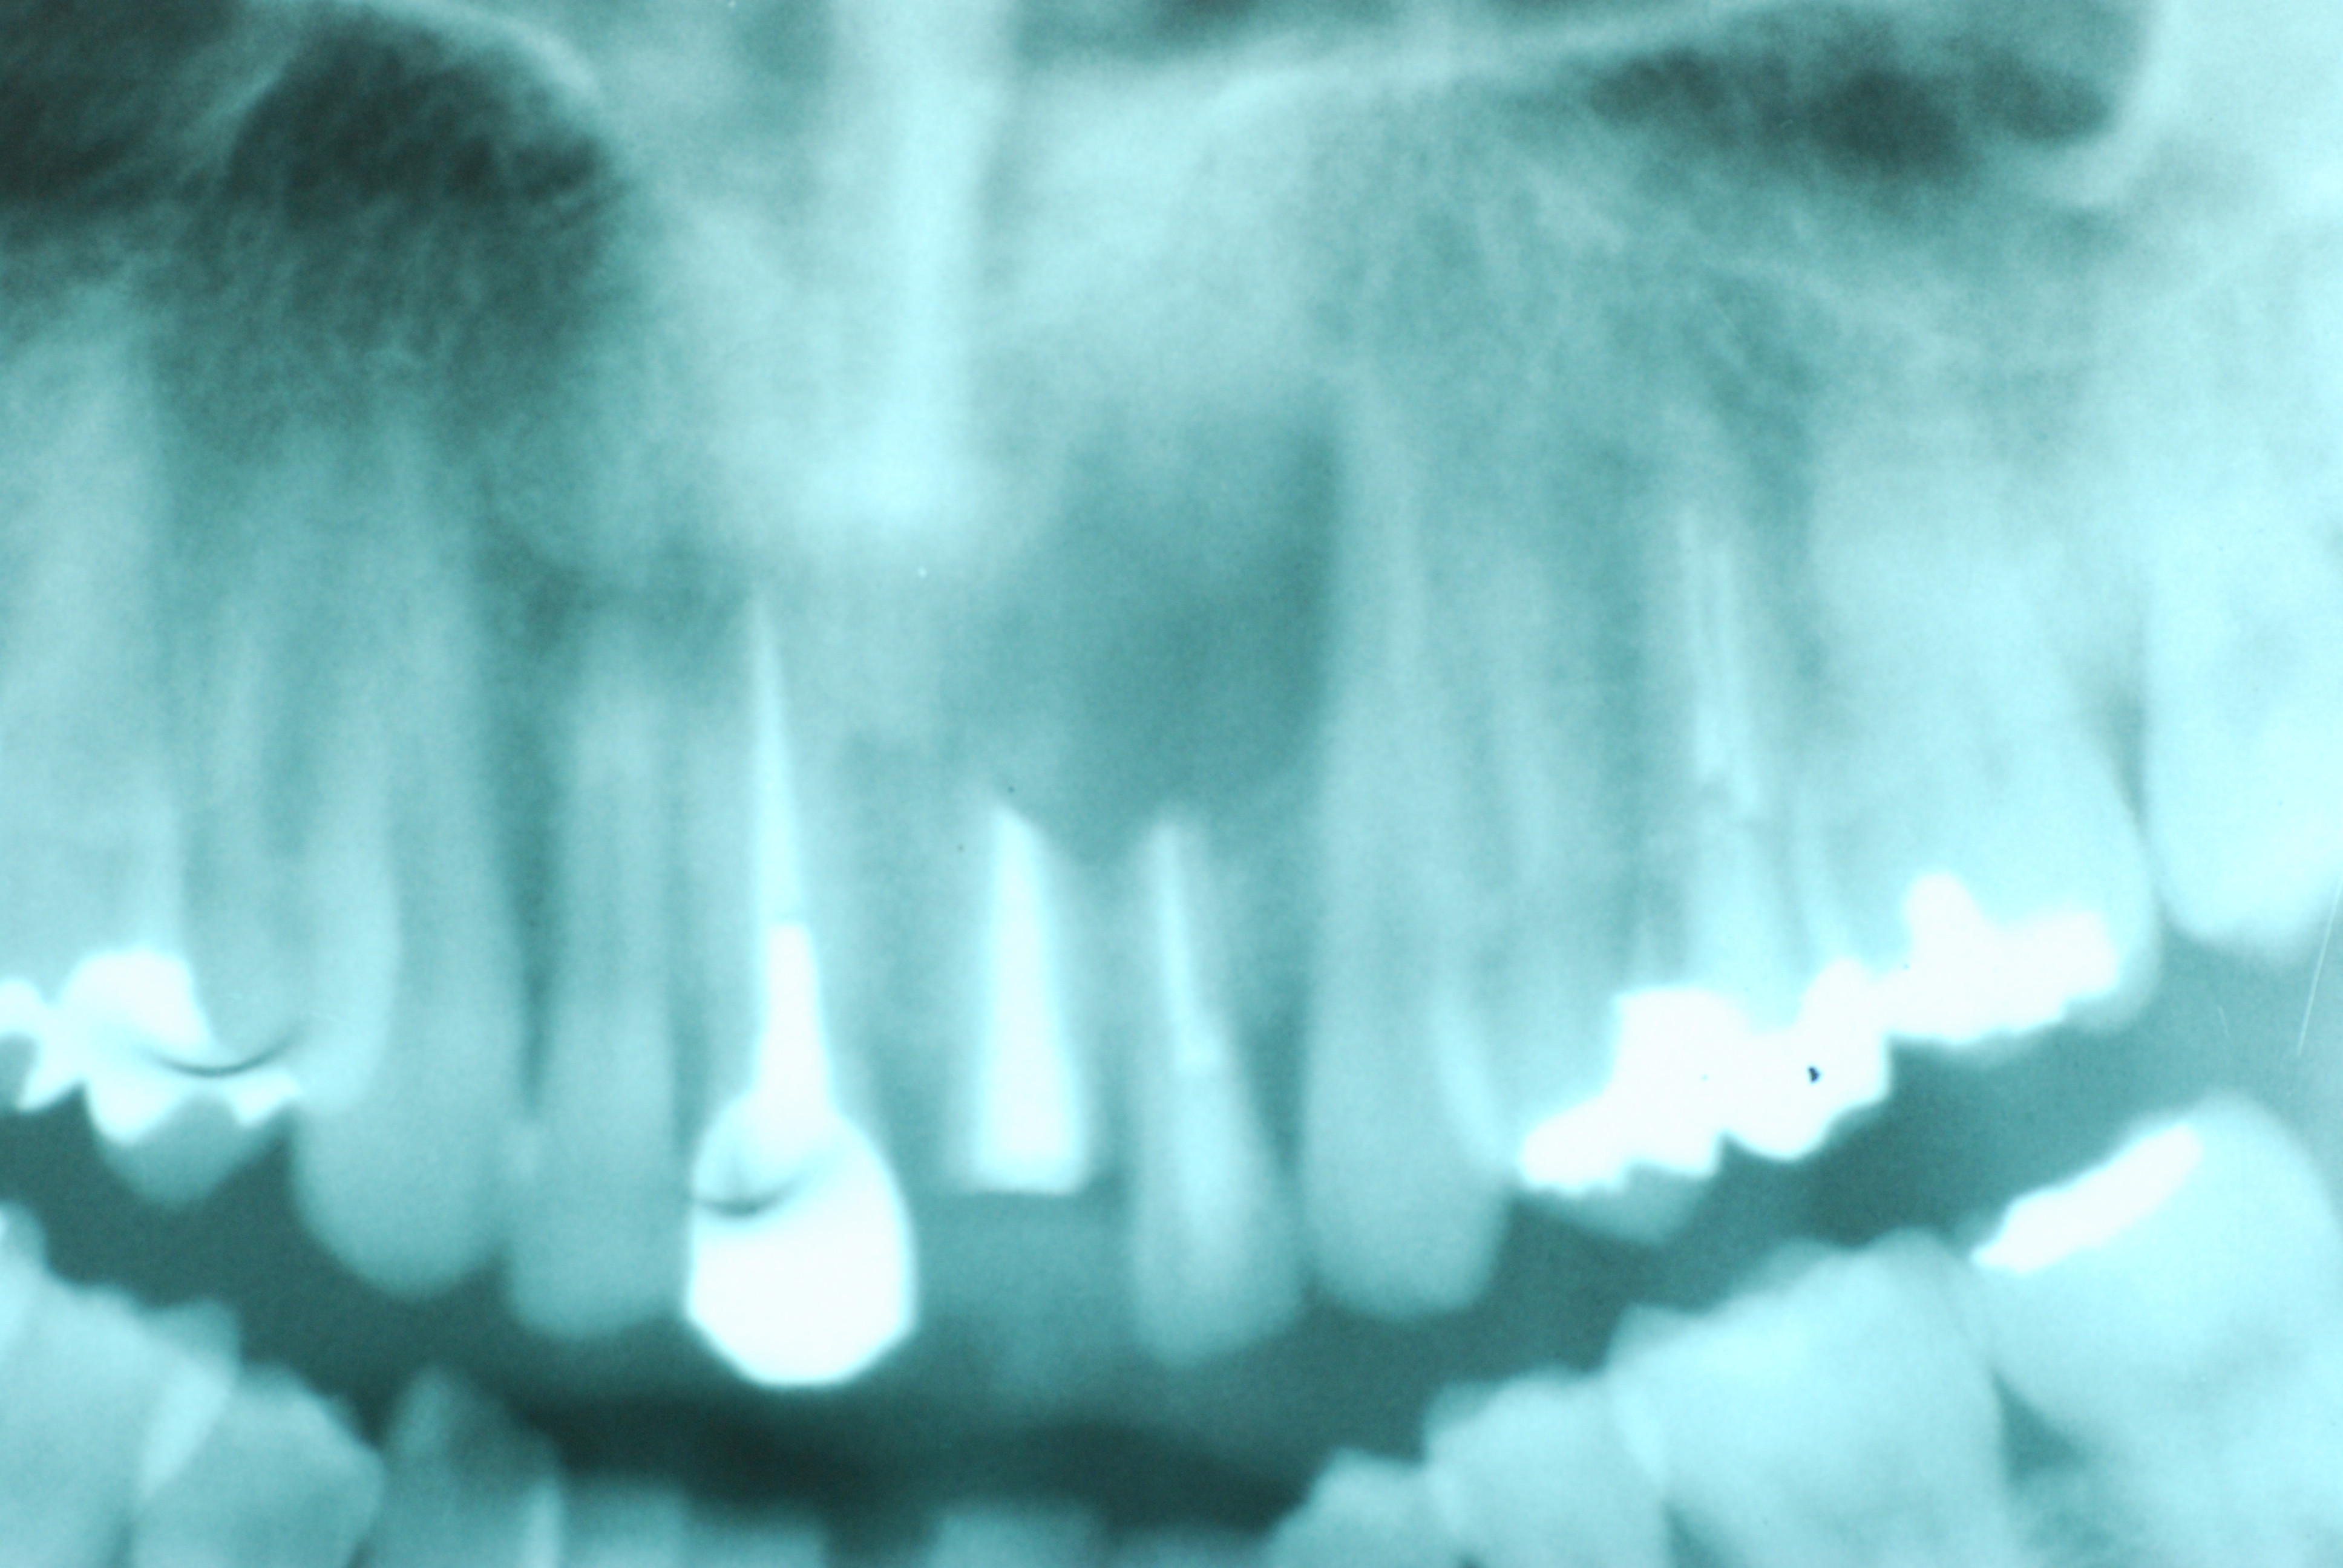

必ずばい菌が侵入しないようにしてばい菌である虫歯を除去します。

銀歯の下はばい菌だらけです。こういうのはよくあります。取り残しですね。![treatment_05[1]](https://livedoor.blogimg.jp/netdental/imgs/3/a/3ad019d0-s.jpg)